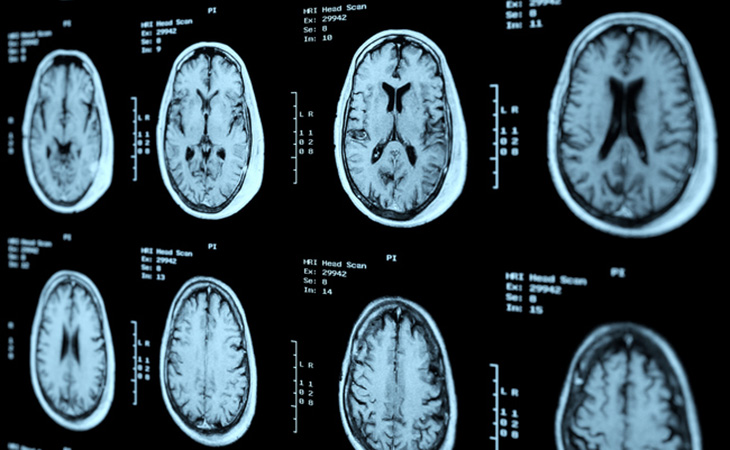

Poor mobility and frequent falls are common in older adults. These symptoms can sometimes be dismissed as typical signs of aging. However, the imbalance and walking issues may be caused by idiopathic normal pressure hydrocephalus (NPH) — the buildup of cerebrospinal fluid in the brain.

Frequent falls and walking issues due to untreated NPH could result in the loss of independence, nursing home placement and higher mortality risk. Surgical implantation of a shunt is the only effective treatment to manage cerebrospinal fluid drainage.